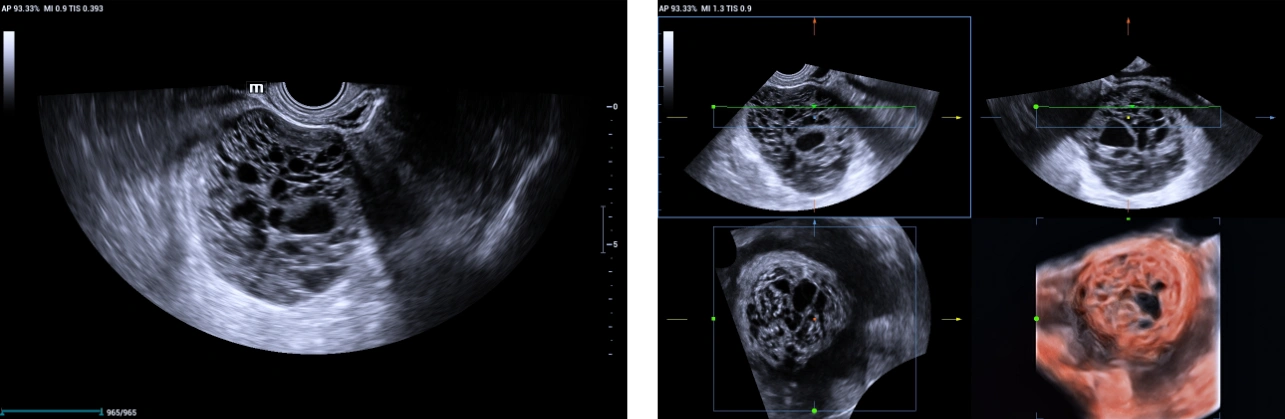

Using Mindray Nuewa I9 Elite edition transvaginal volume transducer DE 11-3Ws, the following findings were noted:

• The left ovary harbors a multi-locular solid mass lesion measuring about 78x63x66 mm at maximum dimension showing multiple irregular (more than 10) locules giving the characteristic Swiss cheese appearance that was well appreciated on volume reconstructed images using Mindray’s iLive pro and Hyaline features.

• On color doppler interrogation on, marked internal vascularity was noted (color score 4). Combination of power doppler and 3D volume ultrasound helped in accurately assessing the mass vascularity and color scoring.

3D Doppler avi clip